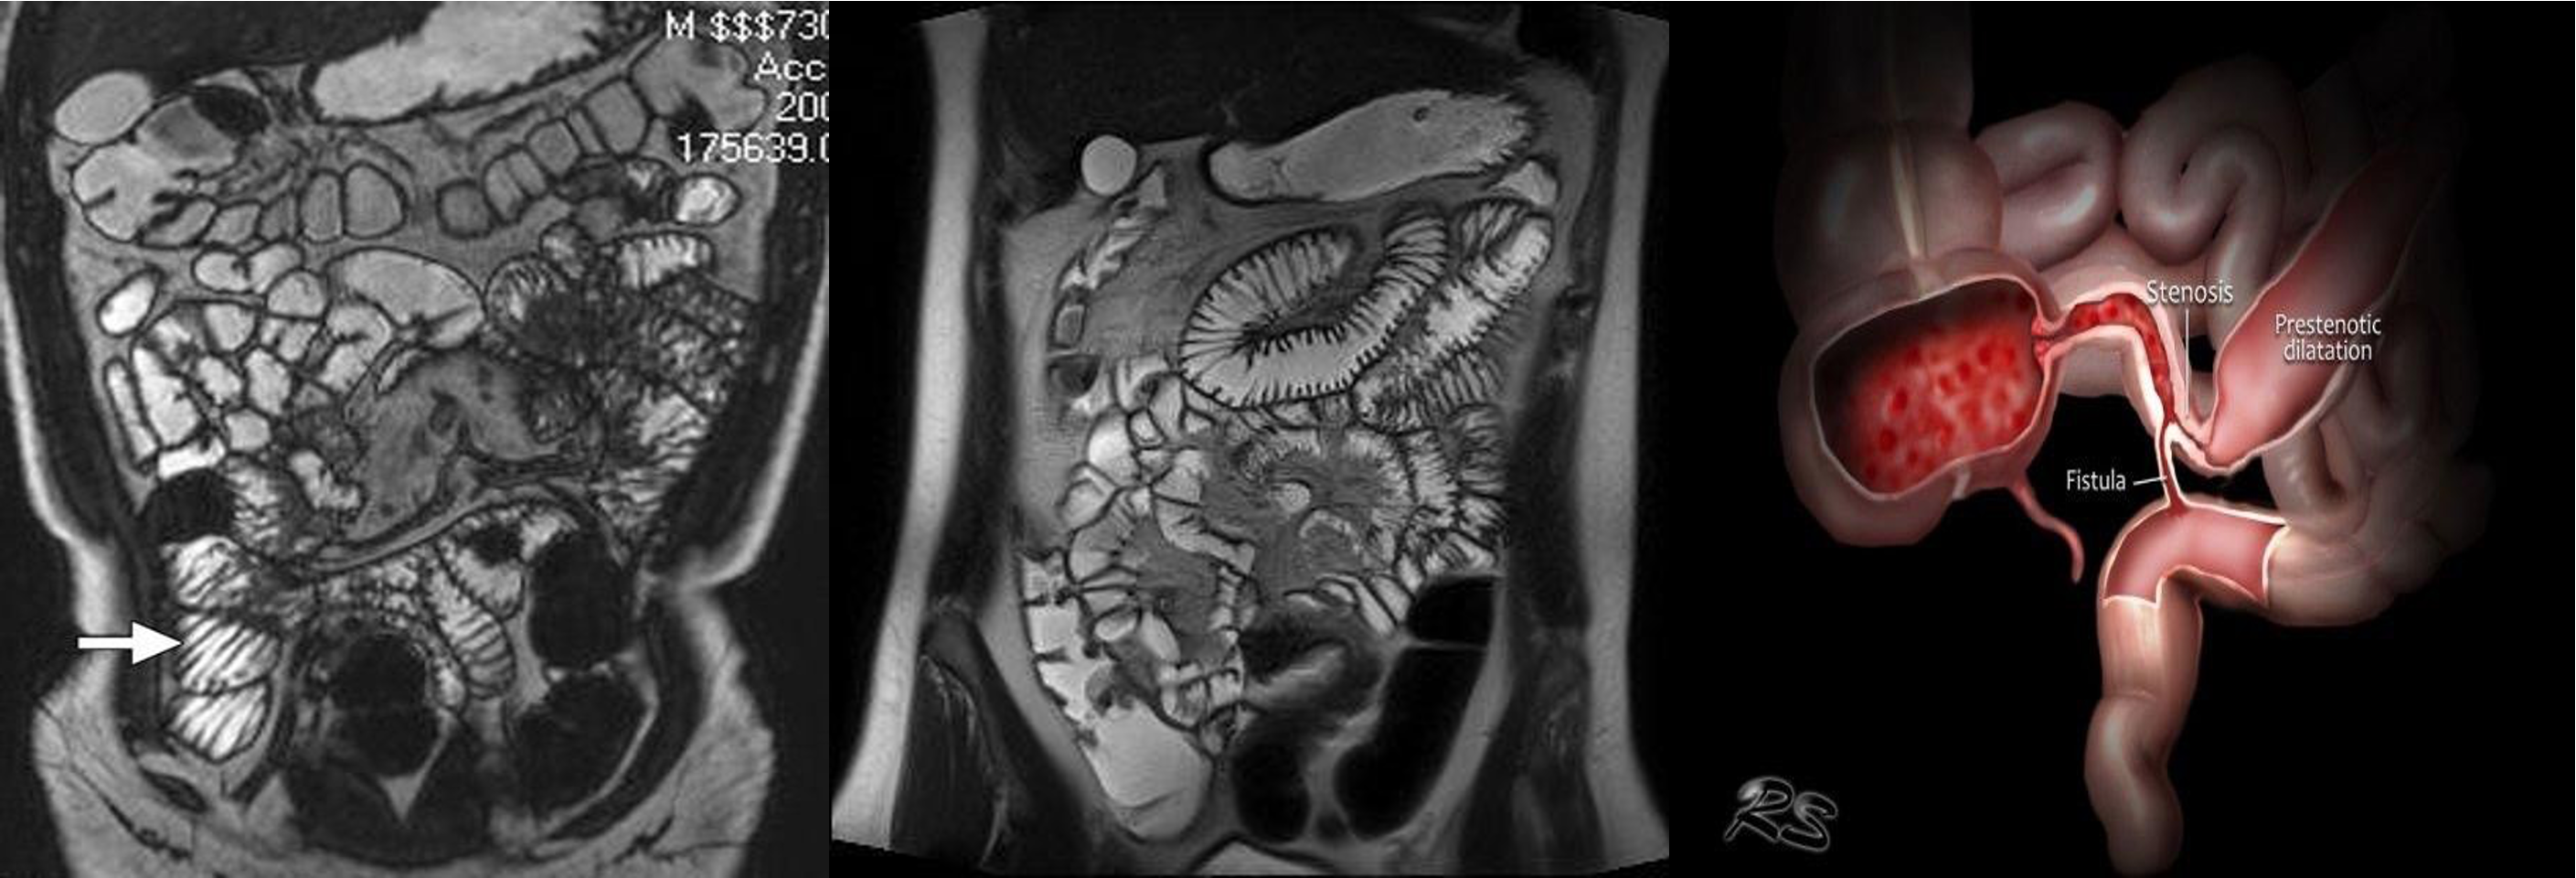

- & 2 MRE -

- MRE (crohn)

- MRE